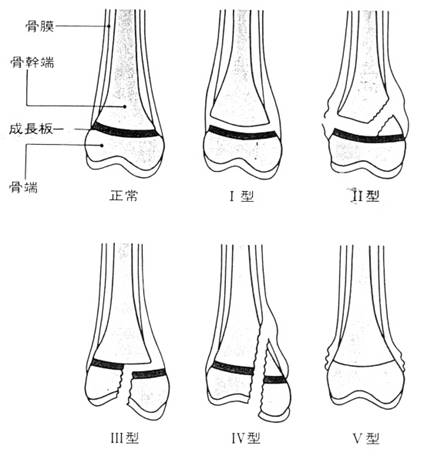

骨端線損傷 Salter-Harris分類

Ⅰ型:骨端線離開。離開が起るのは成長板4層のうちの胞状細胞層。血流を受けてなく離開が起っても出血に乏しく局所の腫脹は軽い。

Ⅱ型:Salter-Harris骨折で頻度が1番。離開は骨端に剪断力が加わった側に起こり成長板の大部分を通過する。

そして反対側の近くで骨幹端に向かって三角形の骨片を形成する。整復は容易。

Ⅲ型:骨端線が部分的に閉じかかっている部分に起こりやすい。予後は良好だが関節内骨折であるため、十分な整復位が得られないと

関節面に不整が起こることがある。

Ⅳ型:Ⅳ型では骨折線は関節面に始まり骨端、成長板を通過して骨幹端に達する。観血的整復がなされる。

Ⅴ型:狭い意味での骨端線障害である。長軸方向の力が加わって成長板に挫滅が起こった状態。